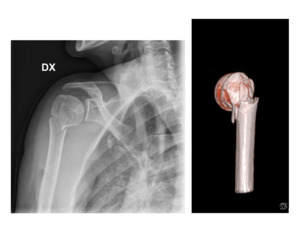

We identified eighty patients eligible for the study, according to the inclusion and exclusion criteria. Sixty-four patients (80%) were available for a telephonic evaluation, whether sixteen patients (20%) were lost at the follow-up and were excluded from the study. Mean age was 74 years (66-85). There were 19 males and 45 females. Mean follow-up was 4 years (1 to 7). Fracture types were classified according to Neer as two-part fracture in 6 cases (9%), as three-part fracture in 25 cases (39%), as four-part fracture in 33 cases (51%). According to the CV criteria, the severity grade was evaluated as low in 23 cases (36%), medium in 13 cases (20%) and high in 28 patients (44%). Fifteen patients (23,5%) were treated conservatively, with immobilization for 4 weeks before to start physiotherapy; forty-nine (76,5%) surgically. Three patients (4,5%) were treated with closed reduction and percutaneous osteosynthesis with Kirschner wires. One (1,5%) patient was treated with open reduction and synthesis with a locking plate. Nine patients (14%) were treated with an endomedullary autologous iliac crest bone graft and locking plate. Eight patients (12,5%) were treated with a titanium endomedullary cage and locking plate.18 Twenty-eight cases (44%) were treated with reverse prosthesis. In the immediate postoperative period, we did not observe any vascular complications. One patient need postoperative intensive care. In three patients we observed a postoperative temporary axillary palsy. Mean inpatient time was 3,5 days (±2,5). SST values are reported in table 1. The statistical regression test demonstrated that the severity grade (p<0,05) correlates better than the Neer classification (p=0,35) to the type of treatment. Indeed, no patient with a low severity grade was treated with a reverse prosthesis and the 85% of the conservatively treated patients are in the group graded as low severity grade. On the contrary, reverse prosthesis and conservative treatment were used with a similar frequency in 2-, 3- and 4- part fractures. In particular, we observed several 2-part fractures with high (Fig. 1) and medium (Fig. 2) severity grade characterized by calcar fracture and lateral comminution. On the other side, better SST values were not statistically associated to a lower severity grade neither to the Neer classification. Only if we calculate the SST values for a specific group of treatment we could find a significative correlation between severity grade and clinical outcomes.